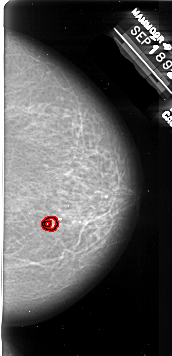

A_1009_1.RIGHT_CC

RIGHT_CC LINES 6406 PIXELS_PER_LINE 3091 BITS_PER_PIXEL 16 RESOLUTION 42 OVERLAY

FILE: A_1009_1.RIGHT_CC.OVERLAY

TOTAL_ABNORMALITIES 1

ABNORMALITY 1

LESION_TYPE MASS SHAPE IRREGULAR MARGINS SPICULATED

ASSESSMENT 4

SUBTLETY 1

PATHOLOGY MALIGNANT

TOTAL_OUTLINES 2

BOUNDARY

CORE